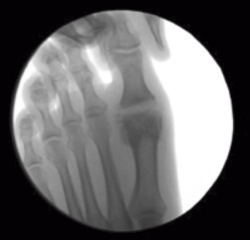

Se debe acceder a la articulación mediante 1 o 2 portales articulares situados a ambos extremos de la articulación a nivel dorsal (Figura 1). Deben ser unos portales un poco más grandes de lo normal, de 2 a 3 mm, que nos permitan un buen acceso a la articulación y poder extraer los fragmentos de cartílago que no podamos triturar. La fresa a utilizar es la Shannon® larga o Shannon® 44, que permite acceder a toda la articulación (Figura 2). En ocasiones, podemos utilizar la fresa de tipo pino (llamada así por su forma).

Figura 1. Portal articular a través del cual la fresa Shannon® elimina el cartílago y prepara las superficies articulares.